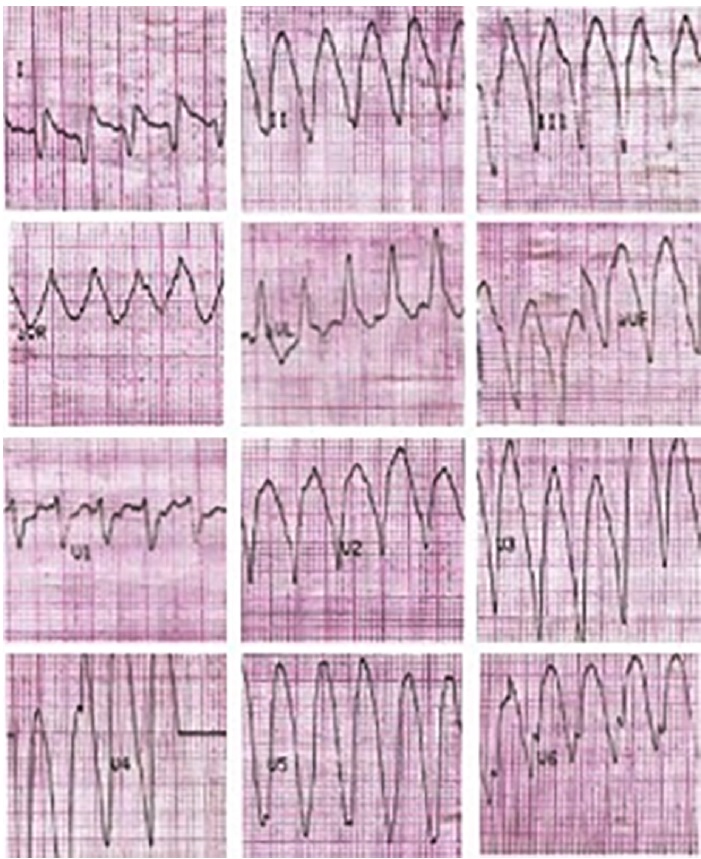

Presentamos un paciente de sexo masculino de 30 años, con antecedentes de miocardiopatía dilatada isquémico-necrótica no ateroesclerótica, con fracción de eyección ventricular izquierda (FEVI) reducida (35%) y aneurisma ventricular (Figura 1) por lesión iatrogénica, extrínseca, tras la sutura de la arteria descendente anterior, luego de una herida de arma de fuego y cirugía de urgencia. Evoluciona posteriormente con varias internaciones por episodios recurrentes de taquicardia ventricular monomorfa sostenida (TVMS) (Figura 2a) por lo que se decide colocación de un dispositivo cardiodefibrilador implantable (CDI) y ablación del sustrato, con evolución favorable.

Fig. 2a Taquicardia ventricular monomorfa con complejo QRS ancho, regular, monomorfa a 190 lpm, con origen apical compatible con el aneurisma ventricular